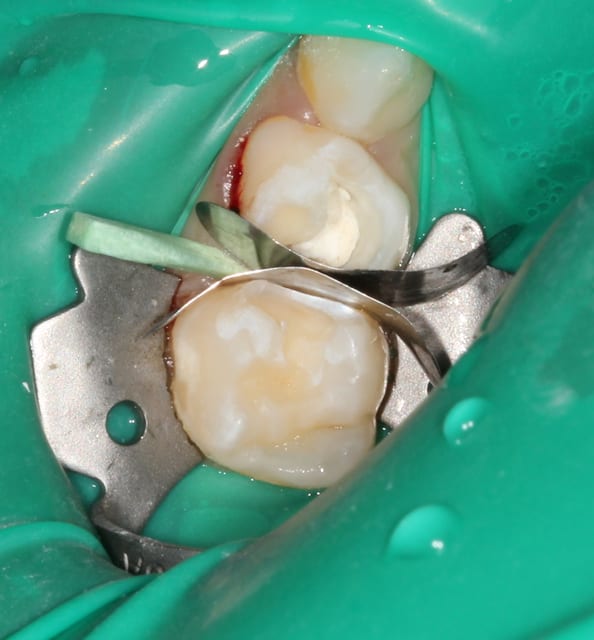

Oui. Les coins surtout sont parfaits car ils sont assez compressifs pour stopper tout saignements proximal, très fréquents chez l'enfant.

Je soigne exclusivement des enfants et toujours sous digue. Comme je te le disais plus haut : cela ne prend pas plus de 30 secondes et ce temps "perdu", tu le regagnes largement derrière.